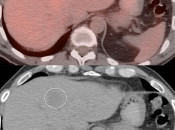

Despite the strong desire for quantification of metabolic activity via the SUV, the most accurate means of distinguishing malignancy from benignity ultimately relies on comparison of a potential lesion’s activity to the background uptake on the scan, its “relative uptake”.

Comparison is most frequently made to uptake within the liver, the mediastinal blood pool or to the organ within which a potential lesion is located.

This comparison can be made by visual assessment or by SUV analysis (comparing the SUV maximum of the lesion with the SUV mean of the liver, blood pool or solid organ).

Relative uptake is particularly useful for assessing lymph nodes, lung nodules and potential lesions located within most of the solid organs in the body.